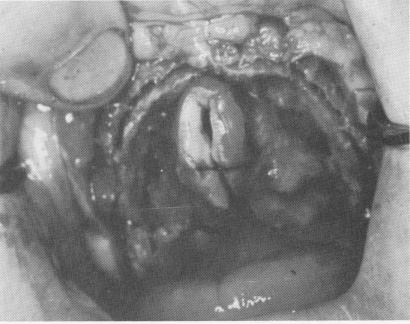

There are times when, because of extremely low-flaring sinuses with numerous areas of bone porosity, individual blades cannot provide adequate support in an edentulous maxilla. Therefore a continuous implant was designed by Linkow and Norman Mulnick. This implant was shaped to the contour of the crest, hopefully creating more retention by acting as a self-splinting device. It was also hoped that the relative instability of those portions of the blade set in porous bone would be compensated for by the fact that there was enough of the rest of the blade in denser bone. A few cases were tried, such as that on the edentulous maxilla detailed here (Fig. 11-166) .

The soft tissue covering the edentulous maxilla was pierced from tuberosity to tuberosity along the crest of the ridge with a sharp scalpel (Fig. 11-167). The tissue was retracted with a periosteal elevator to expose the buccal and labial aspects of the ridge and part of the palatal portion. A groove was created along the center of the ridge from one side of the arch to the other with a No. 700L fissure bur. Its depth was never more than 3 mm. (Fig. 11-168).

Fig. 11-166. An edentulous maxilla with very little bone below the maxillary sinus.

1 Edentulous maxilla with very little bone below maxillary sinus